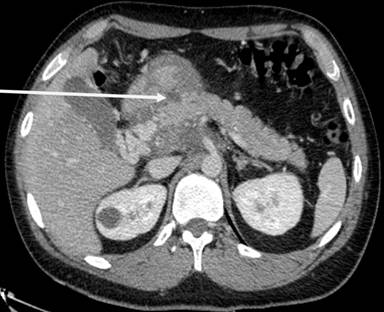

He came to the emergency room because he had felt abdominal pain in the epigastric area for two months, but the pain became constant and with increased intensity. He reported nausea and vomiting, but no modification of bowel habits. Clinical examination revealed stable hemodynamic signs but a marked tenderness with focalized guarding in the right hypochondrium and epigastric region. Laboratory analysis did not reveal anything specific, except elevated lipases at 696 U/L (reference range : 114-286 U/L). Abdominopelvic computed tomography (CT) (Figure 1) and then magnetic resonance imaging (MRI) showed kissing gastric ulcers of the antrum, with the posterior ulcus perforating the gastric wall into pancreatic parenchyma and a Balthazar C associated pancreatitis (Figures 2 and 3). Imaging also disclosed a left portal branch thrombosis and a portal biliopathy (with an amount of thin veins around the main biliary duct) (Figure 4). First, evolution was satisfactory with medical treatment (fasting, gastric protectors, and nasogastric tube). But pain returned with every attempt of food intake. Finally, an endoprosthesis in the pancreatic main duct was placed with a positive result and symptom resolution.

Figure 1. CT showing anterior and posterior gastric lesion with perforation of posterior wall in close contact with pancreatic parenchyma (arrow). |